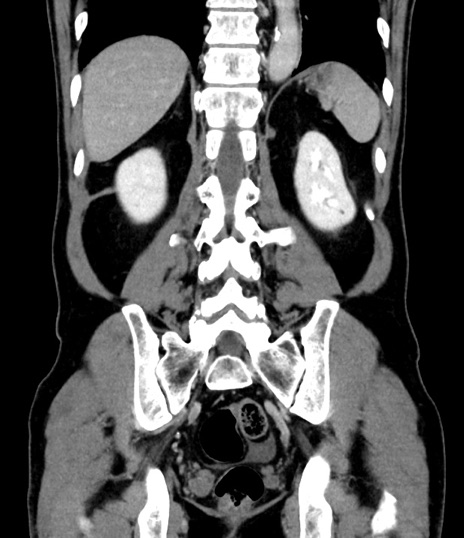

症例8(冠状断像)

【症例】 60歳代男性

【主訴】 黒色吐物

【現病歴】 4日前から嘔気自覚、2日前の朝食後にも嘔気あり、自分で手で嘔吐反射起こし嘔吐したところ血が混ざっていたため受診。

【既往歴】 5年前汎発性腹膜炎を伴う急性虫垂炎で手術、高血圧、前立腺肥大症、高脂血症

【身体所見】 腹部正中に手術癩痕あり 腹部平坦・軟圧痛なし膨満感あり

【データ】WBC 8400、CRP 4.54